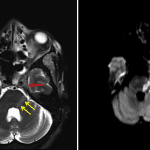

- Abnormal T2 hypointensity in the left foramen ovale and left Meckel’s cave with restricted diffusion involving the cisternal segment of the left trigeminal nerve extending into the left dorsolateral pons and left Meckel’s cave

Findings consistent with perineural spread of infection along the V3 branch of the left trigeminal nerve from the left masticator space, through foramen ovale, and involving the left Meckel’s cave with further retrograde extension along the cisternal segment of the left trigeminal nerve into the left dorsolateral pons.